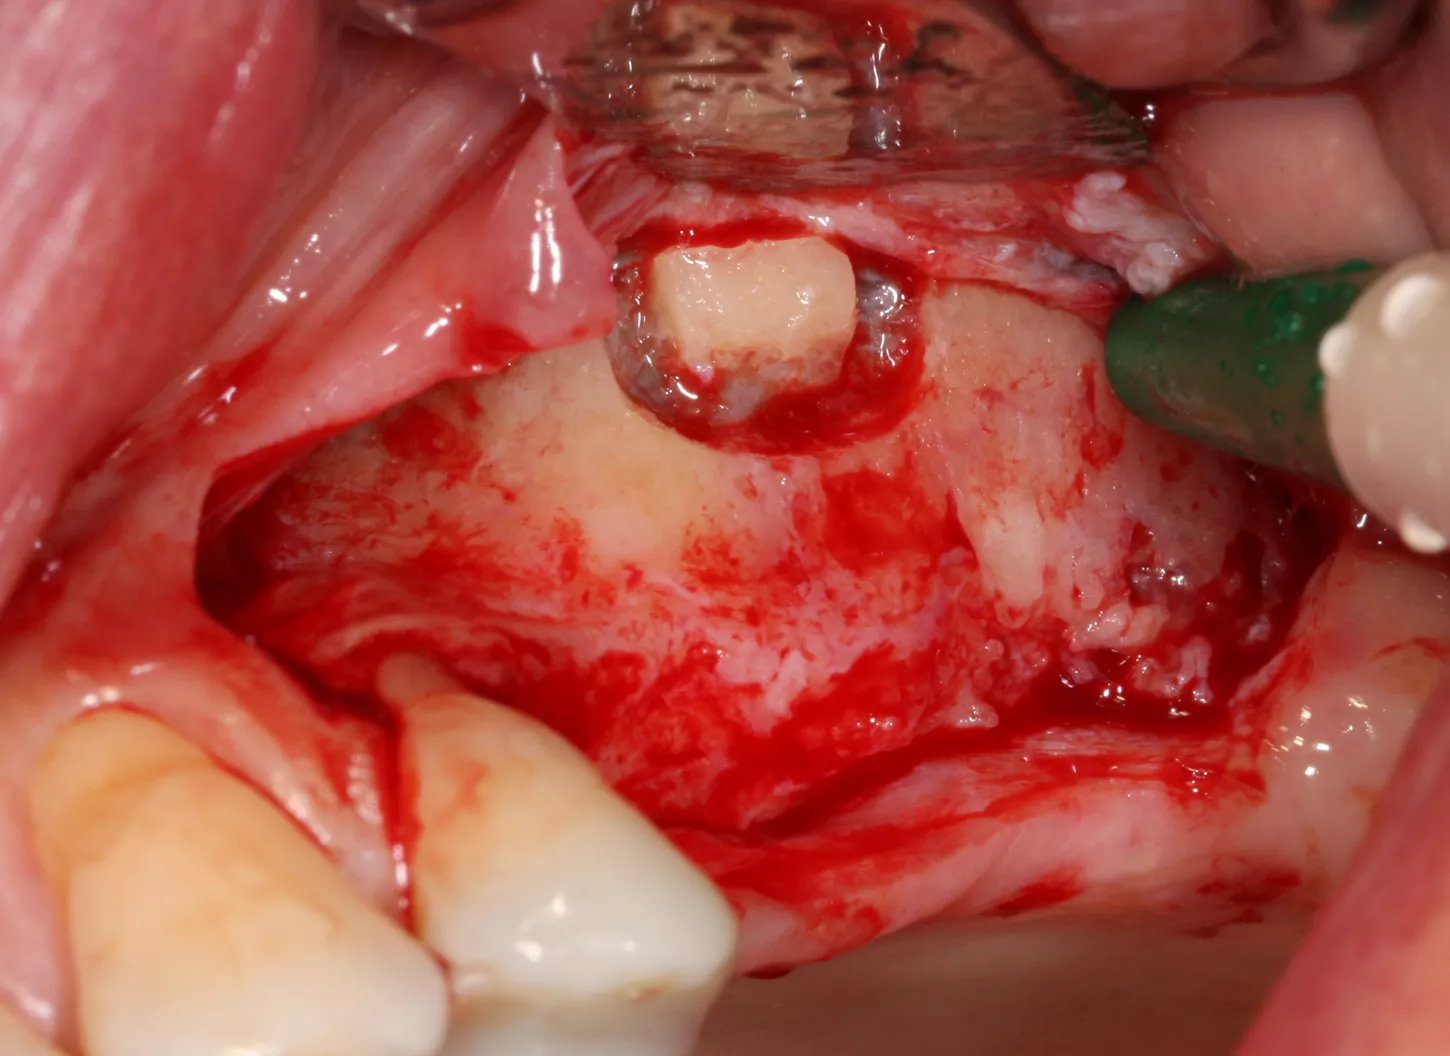

9-10-11. The patient had D3 bone density. Hence an undersized drilling protocol was employed, the final drill diameter being one less than that of the implant. The green drill was used for the 25 implant (diameter 3.4) and the red one for the 26 (diameter 4.0).

9

10

11